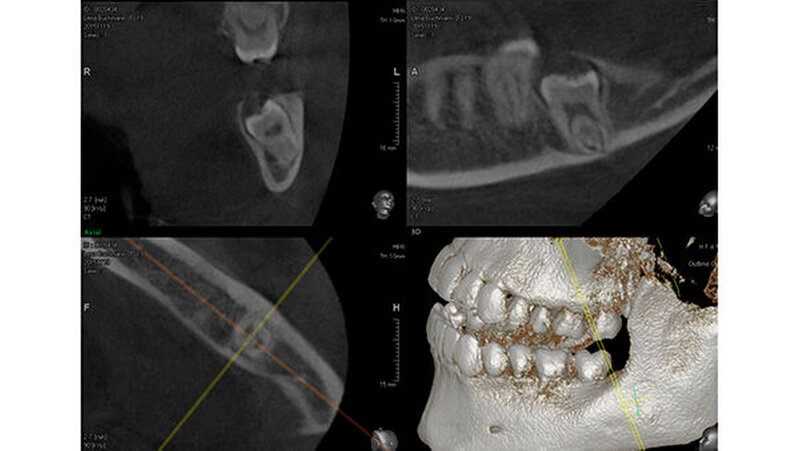

Aufgrund der engen Lagebeziehung der Weisheitszähne 38 und 48 zum Nervus alveolaris inferior (Abbildung 1) wurde zur weiterführenden Diagnostik eine digitale Volumentomografie (DVT) in der Praxis von Dr. Burkard Langenfeld in Friedrichshafen durchgeführt (Abbildungen 2 und 3).

Auf der DVT-Aufnahme zeigte sich vor allem in regio 48 der extrem Nerv-nahe Bezug und eine sehr tief impaktierte Lage des Zahns zum Ramus. Aufgrund dieser Befunde wurde eine Verplattung wegen der möglichen iatrogenen Bruchgefahr des Unterkiefers zur Stabilisierung des Unterkiefers mit der Patientin präoperativ besprochen.